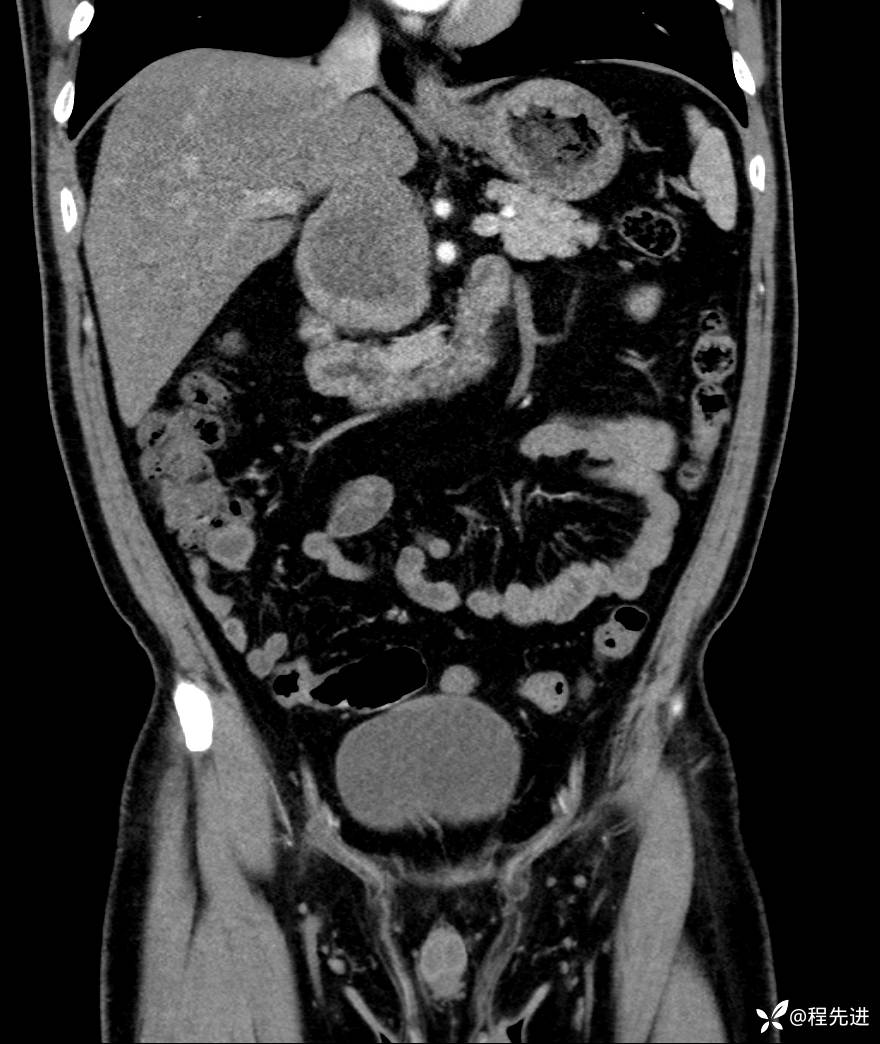

【腹盆】特别精彩病例|发现腹膜后肿物1月余

主诉:发现腹膜后肿物1月余

现病史:患者1月余前查体,行超声检查提示:后腹膜囊实性肿块;慢性胆囊炎伴胆囊内结石;无腹痛腹胀,不伴腹泻发热等;偶感腰背部酸痛。

CT平扫+增强: